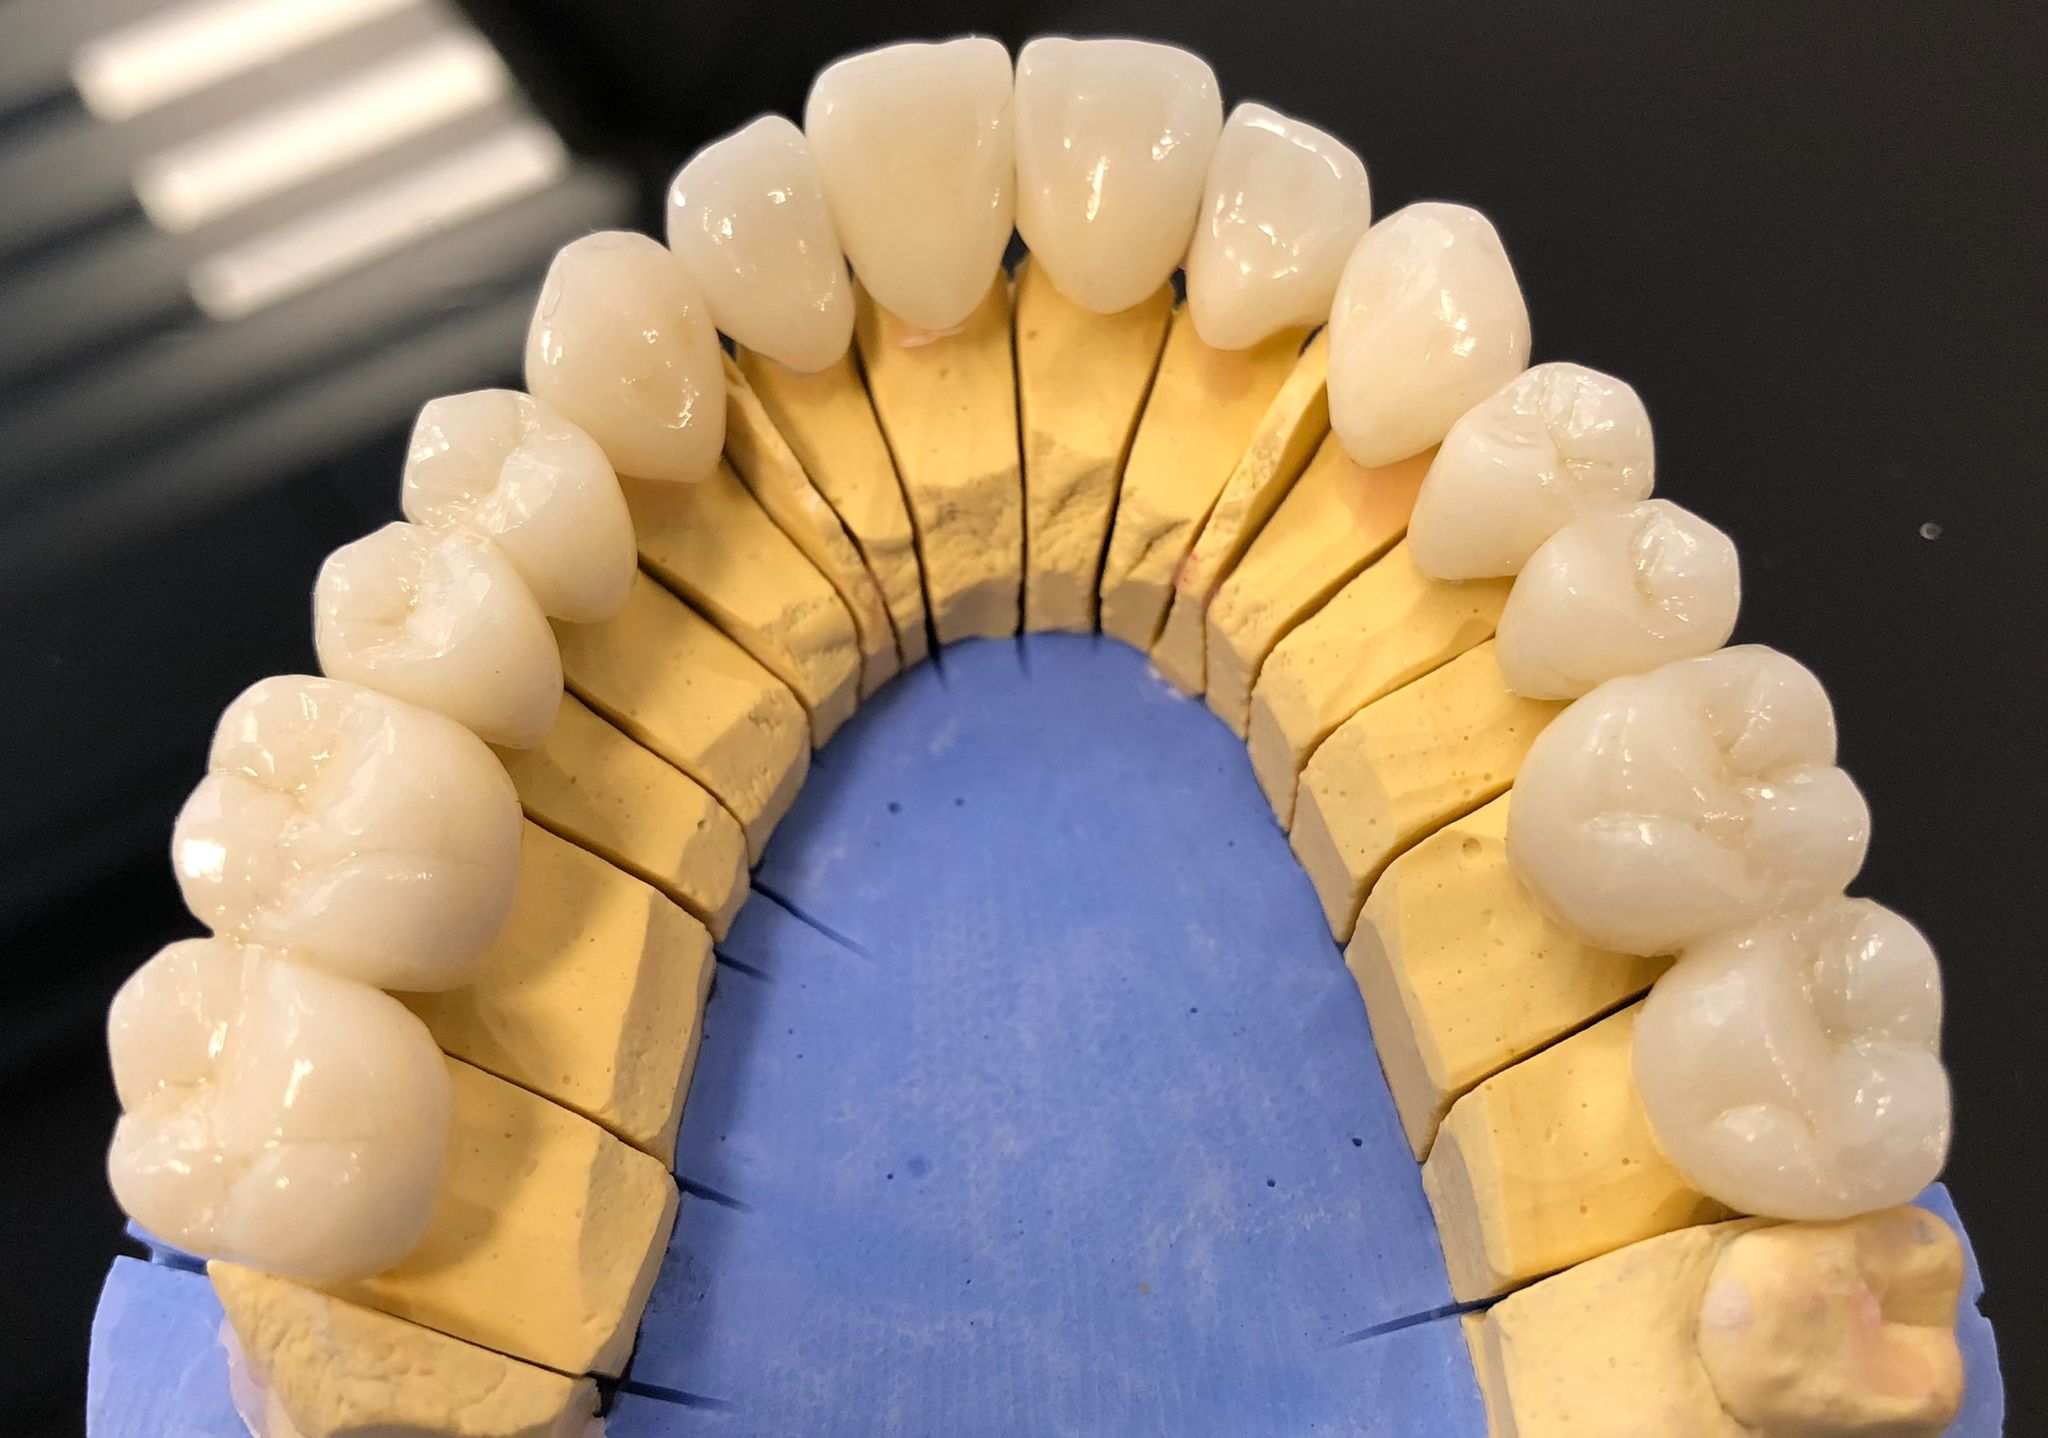

Zirconio Monolítico

Las coronas de zirconio monolítico están hechas completamente de zirconio, un material cerámico altamente resistente y duradero. Al no tener recubrimiento de porcelana, son menos propensas a fracturas y ofrecen una buena estética, aunque con un aspecto ligeramente menos translúcido que otras opciones. Son ideales para dientes posteriores por su gran resistencia al desgaste.